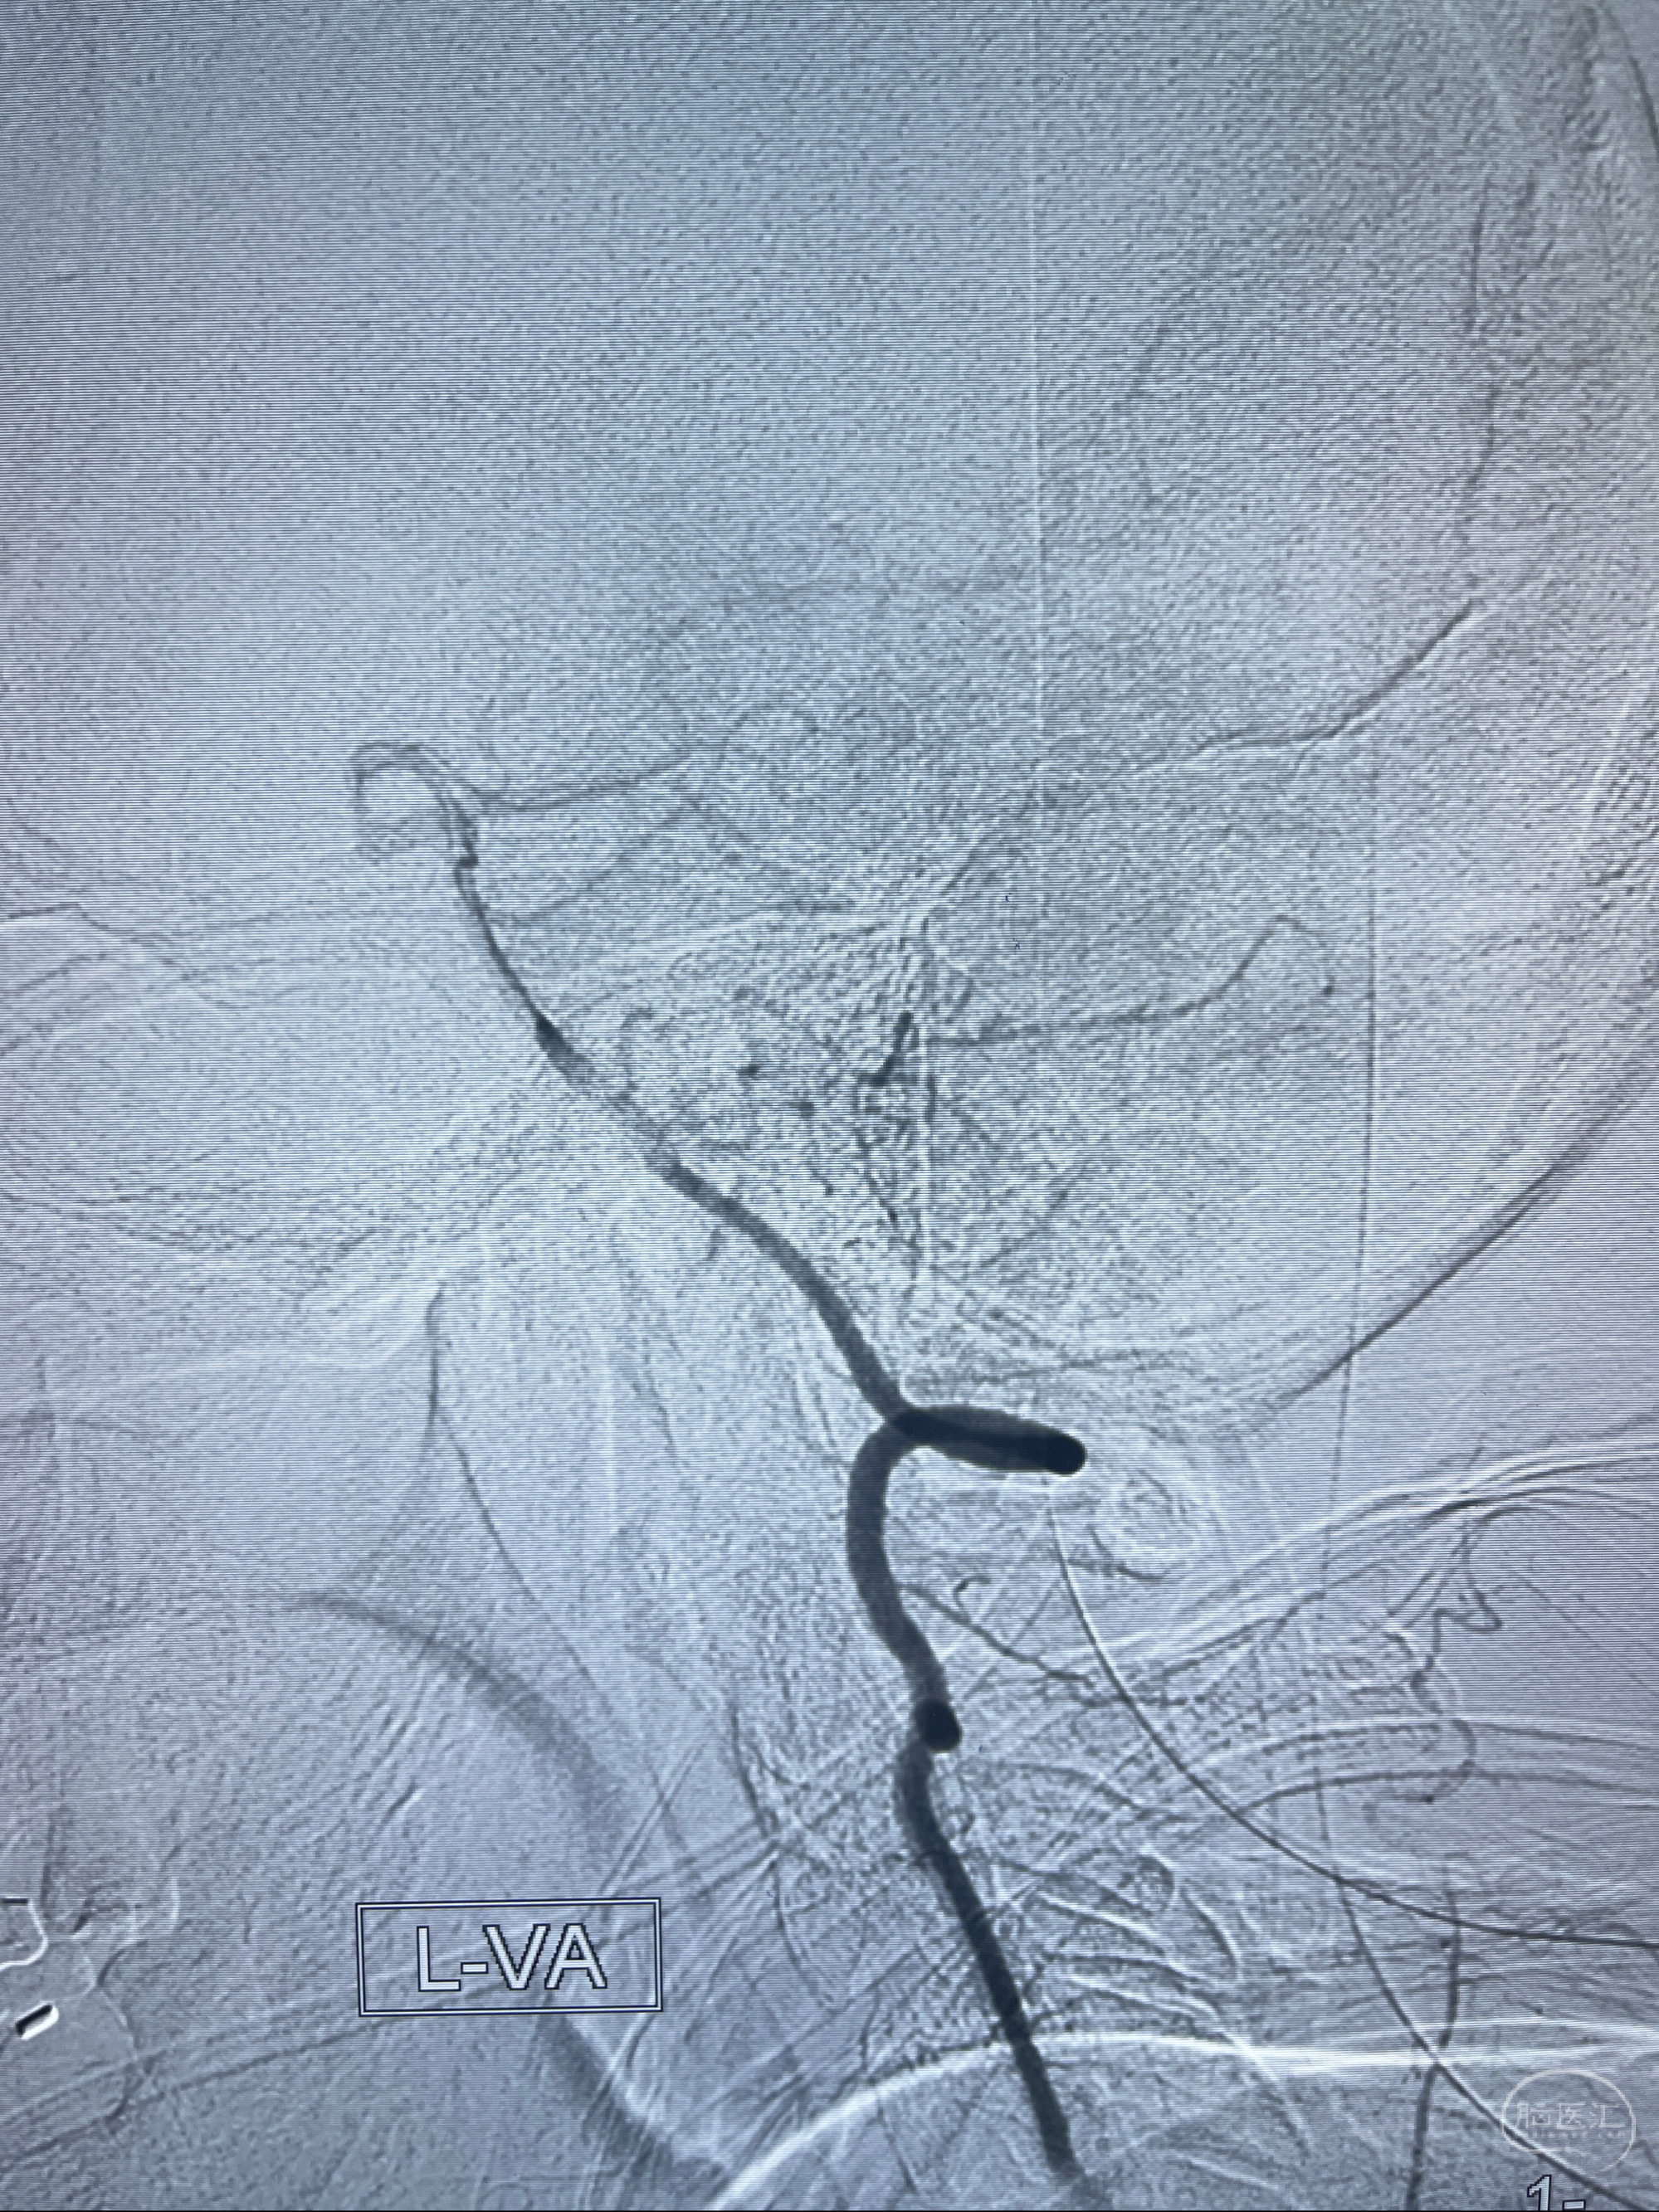

2023-02-15DSA

2023-02-02 沛县人民医院 头颅CTA:大脑动脉环发育变异,头颈部动脉粥样硬化,双侧颈内动脉及椎动脉颅内段多发狭窄;

现病史:患者2023-02-01突发右上肢无力、麻木,伴言语不利,遂至沛县人民医院就诊,急查头颅CT提示:脑实质未见明显异常;后于2023-02-02查头颅CTA提示:大脑动脉环发育变异,头颈部动脉粥样硬化,双侧颈内动脉及椎动脉颅内段多发狭窄;2023-02-04查头颅MRI提示左侧基底节区小腔梗,部分副鼻窦炎症,考虑脑卒中,予以改善微循环、活血等对症支持治疗后建议患者上级医院就诊,并予以阿司匹林、氯吡格雷抗血小板,阿托伐他汀降脂稳定斑块治疗。出院后患者右上肢无力、麻木、言语不利症状反复多次发作;现患者有右上肢麻木,伴口唇麻木,无明显肢体无力,言语流利,另诉偶有心慌、背部疼痛,为求进一步治疗至我科就诊,收治入院。